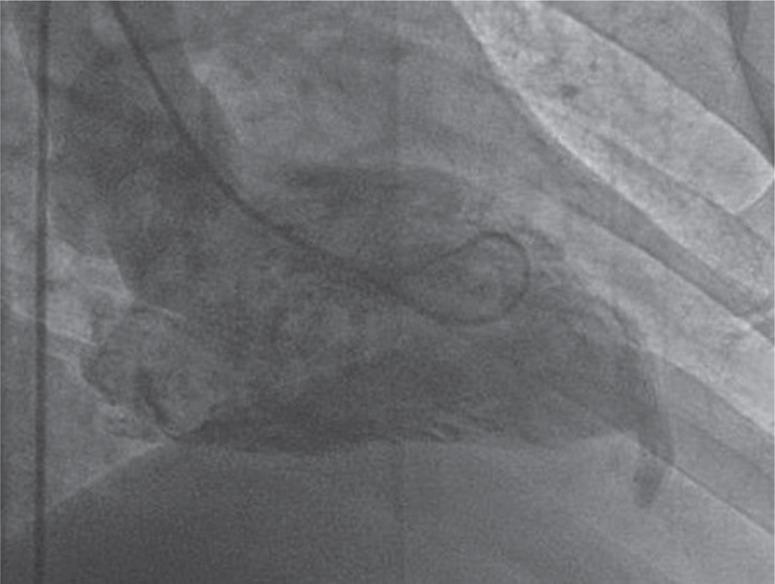

Isolated congenital left ventricular diverticulum presenting as stable angina pectoris and surgical treatment.

Kardiochir Torakochirurgia Pol. 2019 Mar;16(1):44-46. doi: 10.5114/kitp.2019.83946. Epub 2019 Apr 4.